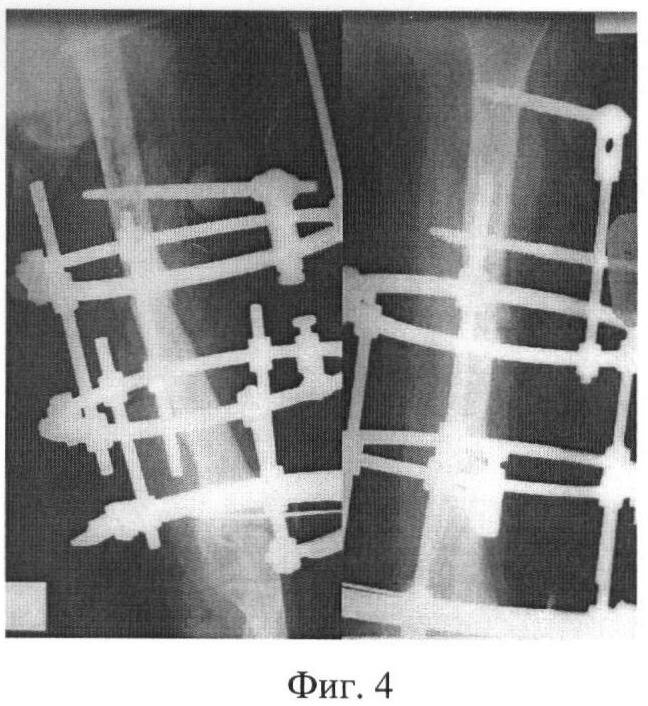

Из анамнеза: травма в быту 01.12.06 г. – упала на левое плечо. Поступила в дежурную ЦРБ, где установлен диагноз: закрытый перелом средней трети левого плеча. После неудачной попытки консервативного лечения и подготовки 5.12.06 г. выполнен накостный остеосинтез левого плеча. Гипсовая иммобилизация 4 мес. Перелом плеча не сросся, сформировался псевдоартроз с межотломковым диастазом отломков 1 см (фиг.1).

Находилась на лечении в клинике травматологии Саратовского научно-исследовательского института травматологии и ортопедии (СарНИИТО) с 23.04.07 г. по 14.05.07 с диагнозом: дефект-псевдоартроз средней трети левой плечевой кости, нестабильный металлоостеосинтез плеча пластиной, односторонний кортикальный дефект отломков 5 см.